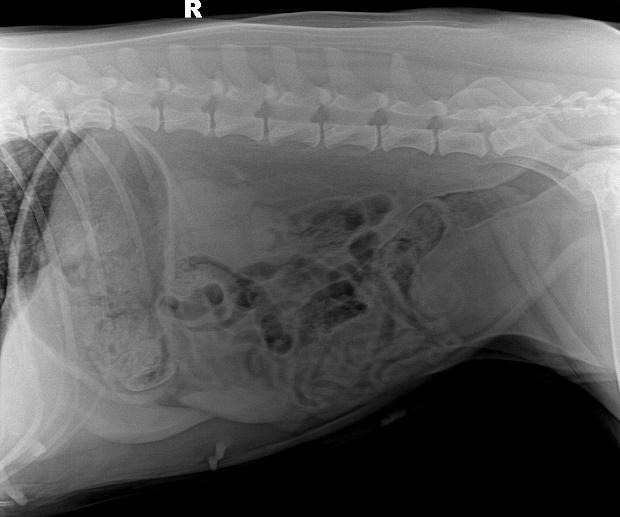

b. X射线检查:针对阻线性较强的物质(如金属、骨头)较容易辨别,针对阻线性与组织密度相似的物体较难确定,但是可以通过消化道灌服造影剂判断是否有阻塞或可包裹物体。

胃的正常大小:胃位于前腹部,隔和胆脏之后。胃排空时位于肋弓以内;从腹底算起,胃的腹侧缘大约在腹腔深度的1/3处。胃充盈时,胃向后向下延伸,与横结肠和腹底部相接。

摆位对

胃内异物(金毛,手术取出6cm大衣扣子)

钡餐4小时后胃内未排空(家猫,线性异物)